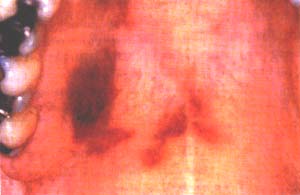

La lesión se ubica de preferencia en el paladar, en la encía y en la lengua 7 , y su tamaño puede alcanzar desde unos pocos milímetros hasta varios centímetros. Como en el SK cutáneo la presentación clínica varía desde una lesión inicial plana de color rojo o violáceo hasta una lesión de aspecto nodular, con o sin la presencia de ulceración (Figras 1-3); su presencia en forma intraósea en los maxilares es rara 8.

Figura 1. Etapa incipiente de un Sarcoma de …Kaposi en paladar de un paciente con SIDA.